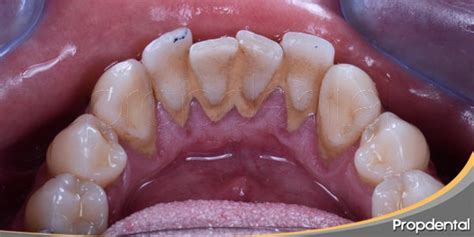

¿Por qué se acumula sarro duro específicamente detrás de los dientes inferiores?

La anatomía oral explica por qué el sarro duro detrás de los dientes inferiores es tan común. Las glándulas sublinguales y submandibulares, ubicadas debajo de la lengua, secretan constantemente saliva rica en minerales directamente hacia la superficie lingual de los incisivos inferiores. La superficie lingual de los dientes inferiores representa una de las zonas más desafiantes para mantener una higiene bucal adecuada. La posición de la lengua, la limitada visibilidad durante el cepillado y la dificultad para maniobrar el cepillo en esta área contribuyen a una limpieza incompleta.